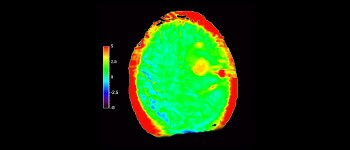

3D APT (Amide Proton Transfer)¹⁻³ is a unique, contrast-free, brain MR imaging method addressing the need for more confident diagnosis in neuro oncology. 3D APT uses the presence of endogenous cellular proteins, to produce an MR signal that directly correlates with cell proliferation, a marker of tumoral activity. 3D APT can support trained medical professionals in differentiating low grade from high grade gliomas and, in differentiating tumor progression from treatment effect⁴,⁵